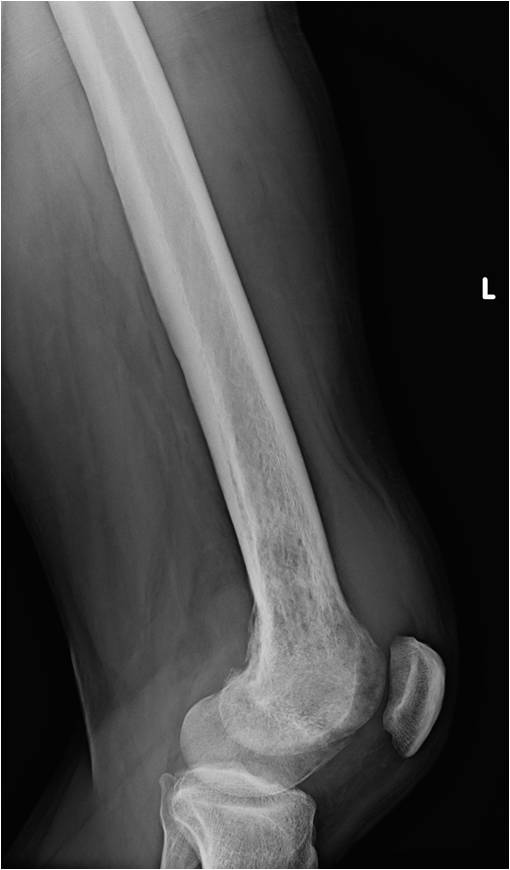

On radiographs, most MFHs of Bone are located in the metaphysis and present as purely osteolytic permeative lesions without a periosteal reaction and without mineralization (Fig. 1 &2). On MR images, MFH of Bone has ill-defined margins usually with cortical destruction of bone and extension into the soft tissues. It is usually hypo- or isointense to muscle on T1-weighted images (Fig. 3) and heterogeneous high intensity on T2-weighted images (Fig. 4-6).

Fig. 1 & 2: Plain x-rays of an MFH of the distal femur. AP (Fig. 1) and Lateral (Fig. 2) view shows a permeative lytic lesion in the distal femur without a periosteal reaction and without mineralization. The lesion is poorly circumscribed.